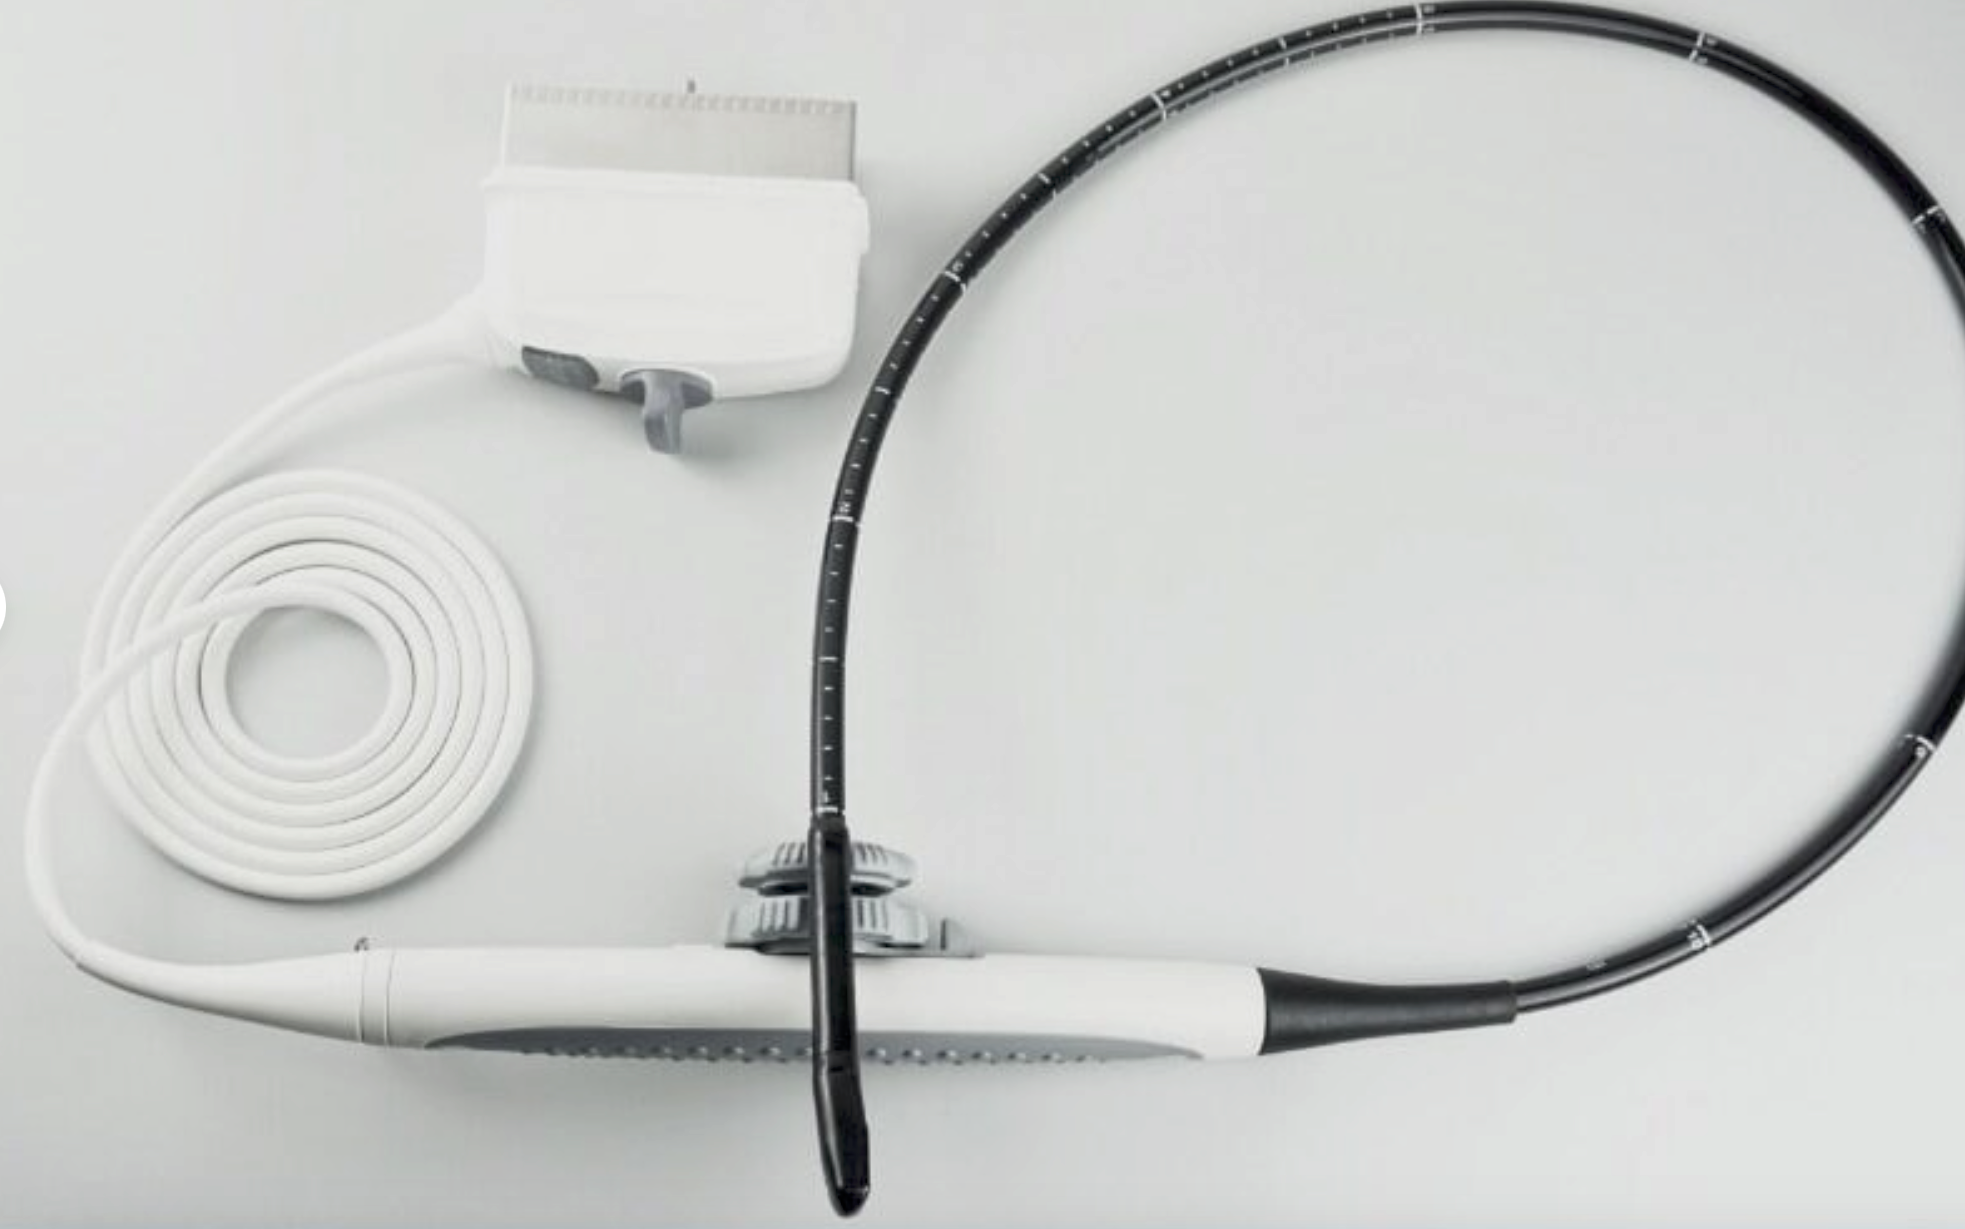

Description

ATL HDI 3500 w/ 2 Probes